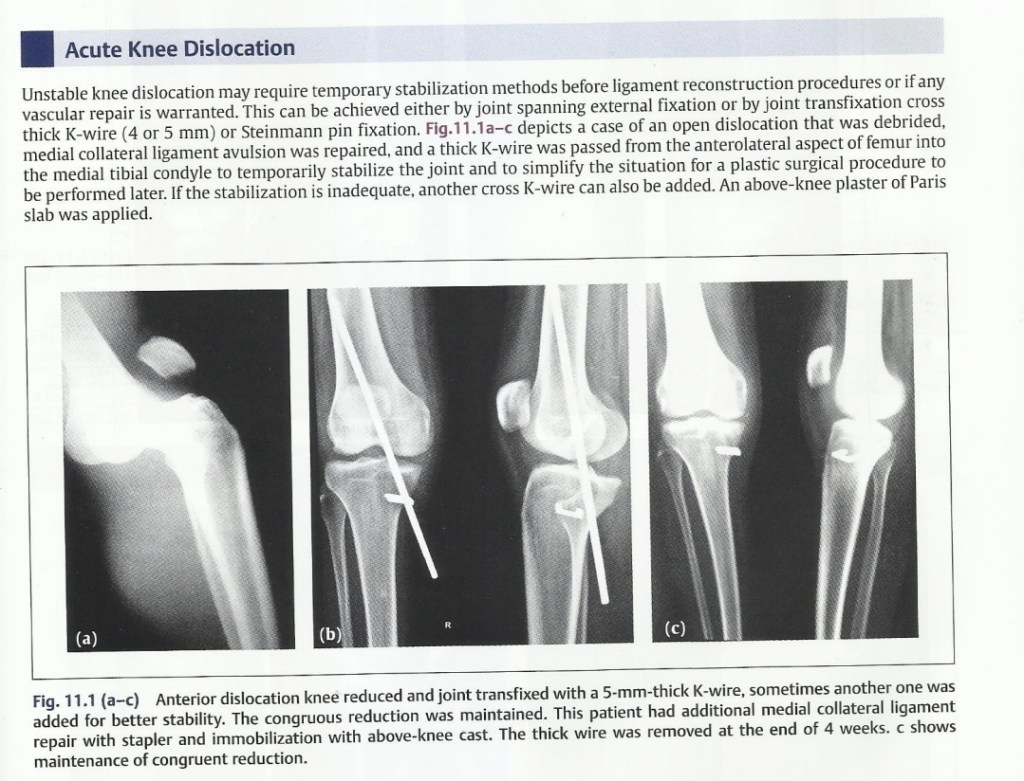

Lecture Knee dislocation & tendon injuries

Lecture Knee dislocation & tendon injuries